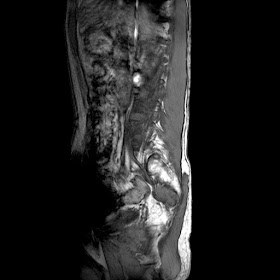

A 35 years old man MRI